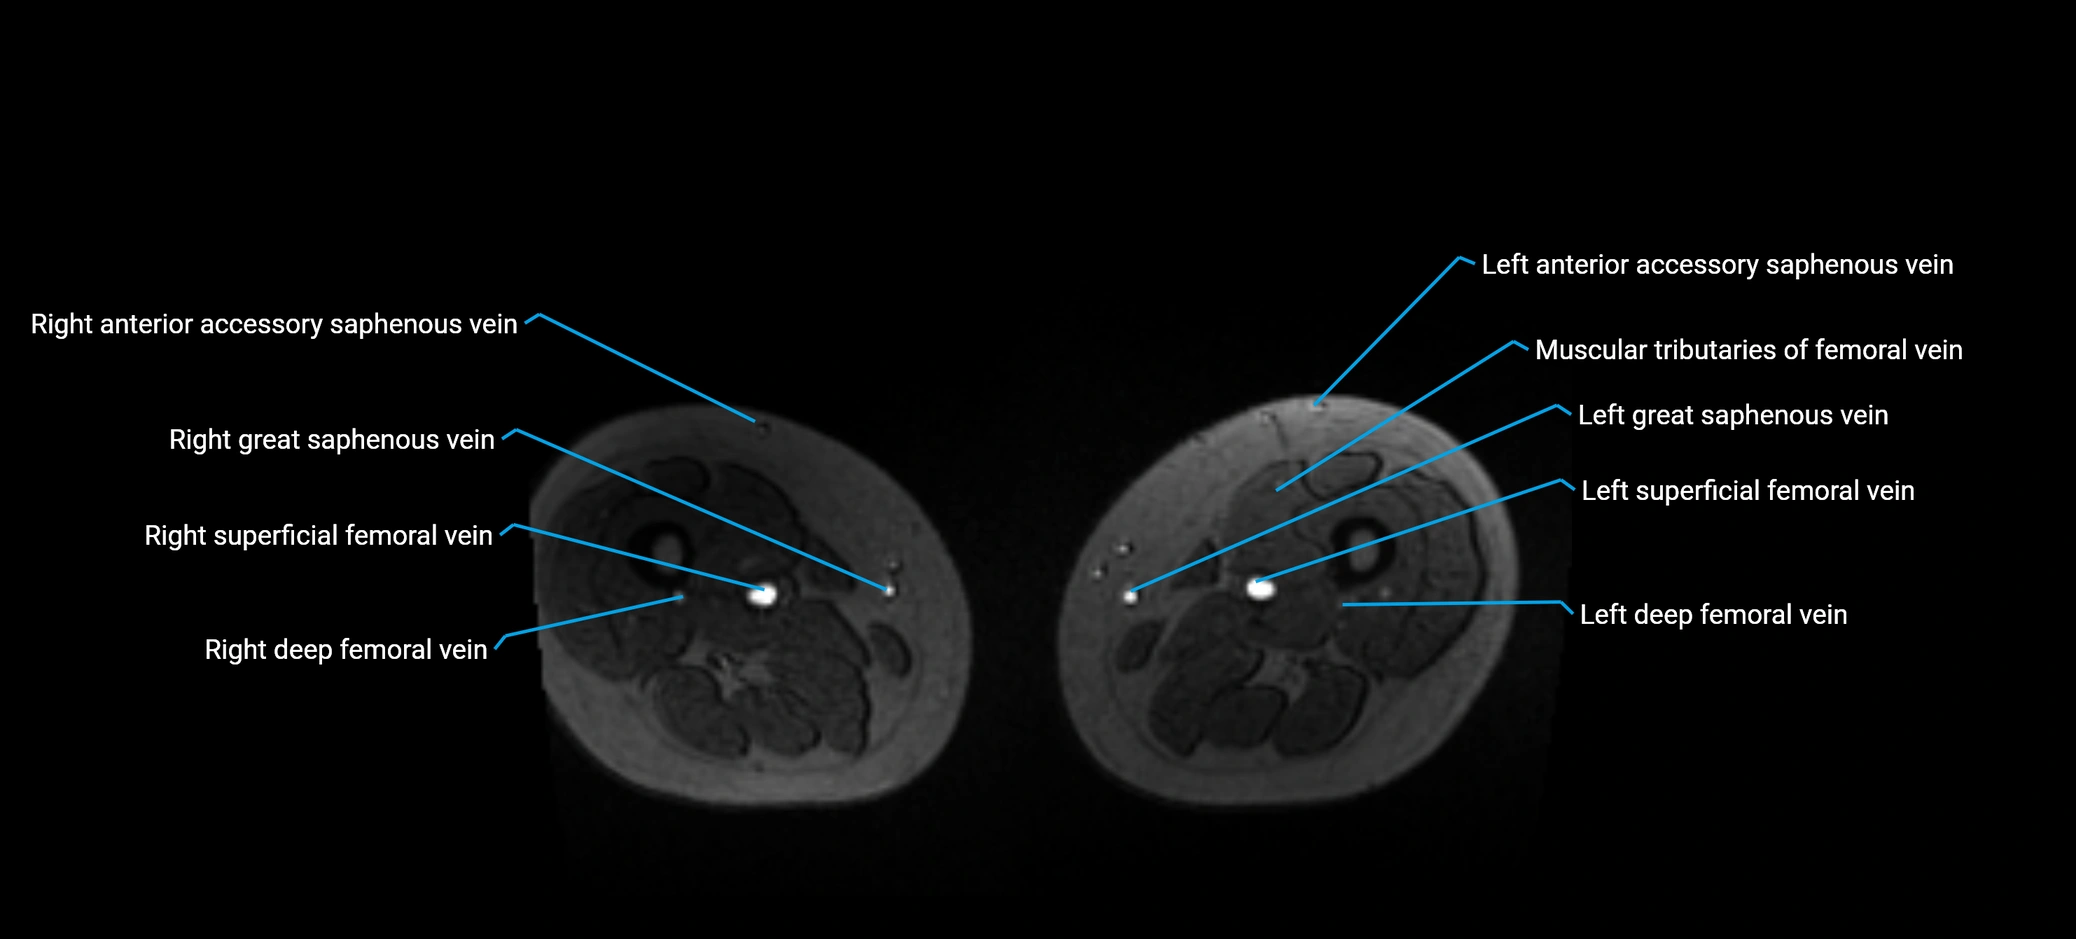

MRI image

image